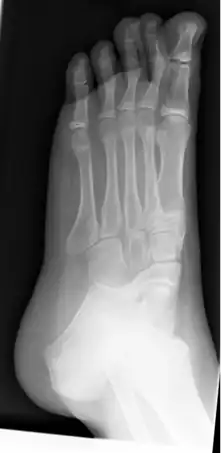

Radiografía de pie izquierdo plano en un niño de 10 años.